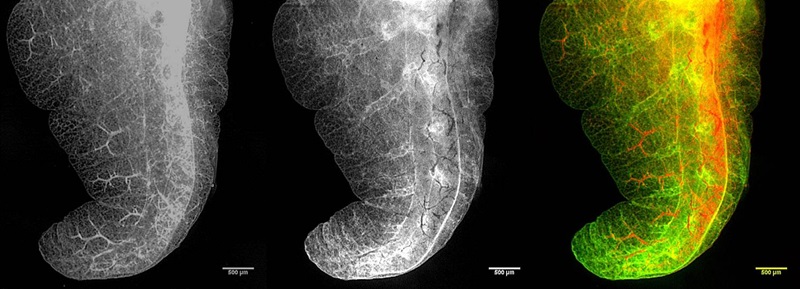

| A rodent's lung, imaged using the SLOT technique. On the left is a simple transmission image produced by a photodiode (PD), in the middle is an autofluorescence image from a photo multiplier tube (PMT), and on the right is a superposition of both signals (red shows PD signal, green shows PMT signal). Credit: LZH. |